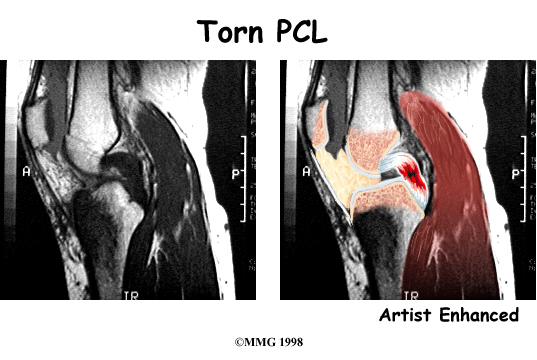

The magnetic resonance imaging (MRI) scan is probably the most accurate test without actually looking into the knee. The MRI machine uses magnetic waves rather than X-rays to show the soft tissues of the body. This machine creates pictures that look like slices of the knee. The pictures show the anatomy, and any injuries, very clearly. This test does not require any needles or special dye and is painless.